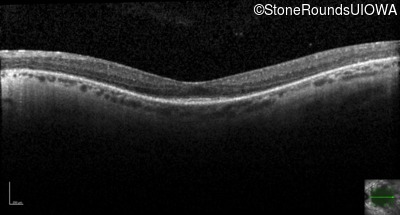

Optical Coherence Tomography - Right - 20/50

Exemplar / OCT Stack

OCT Stack